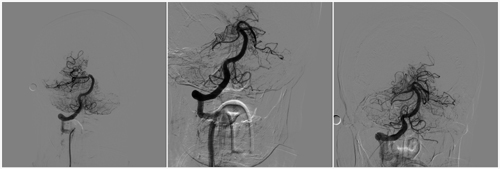

半小時(shí)后,醫(yī)護(hù)人員完成各項(xiàng)術(shù)前準(zhǔn)備,介入科相關(guān)人員全部就位。這時(shí)賈頤主任全神貫注地為進(jìn)行腦血管造影。發(fā)現(xiàn)患者基底動(dòng)脈尖及左側(cè)大腦后動(dòng)脈未見(jiàn)顯影,考慮血栓栓塞可能。趙振偉、李江教授當(dāng)即對(duì)病變血管進(jìn)行機(jī)械取栓,使用SolitaireAB型6mmx30mm支架(ev3公司,美國(guó))置人血栓部位,后退微導(dǎo)管釋放支架,使支架打開(kāi),留置5分鐘后進(jìn)行取栓,復(fù)查造影見(jiàn)左側(cè)大腦后動(dòng)脈顯影,右側(cè)大腦后動(dòng)脈閉塞。對(duì)右側(cè)大腦后動(dòng)脈再次進(jìn)行取栓。